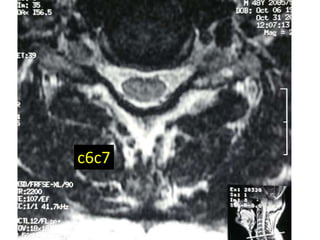

c6c7

48 year old man with right fifth finger pain and numbess